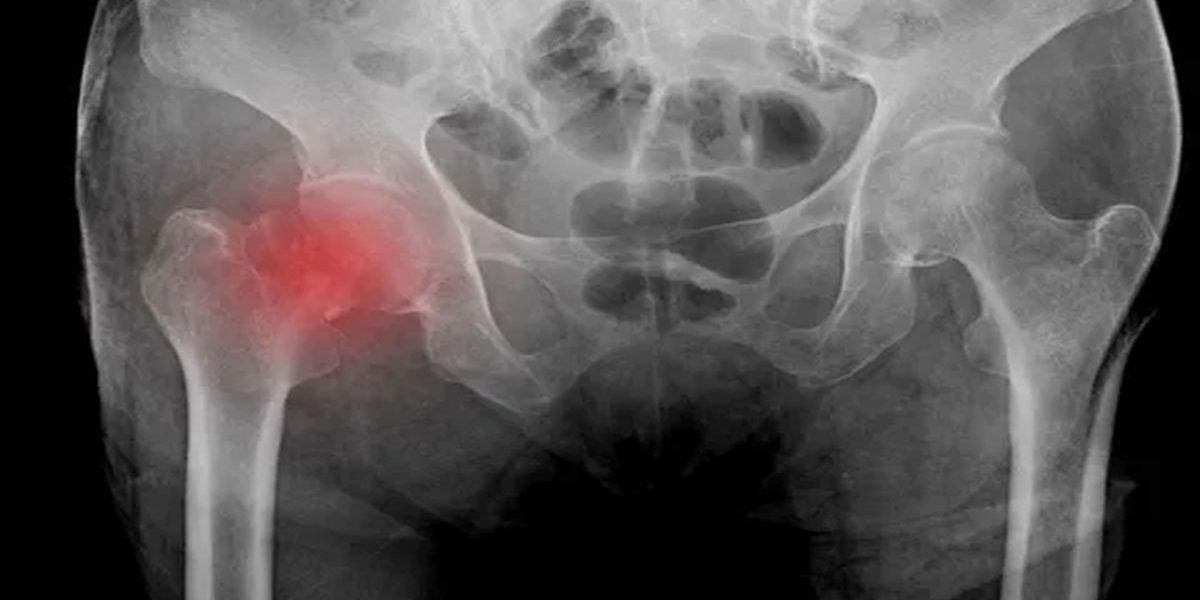

Kalça kırıkları, çoğunlukla düşme veya ani travmalar sonucu ortaya çıkar. Yaşlı bireylerde kemik yapısı zayıf olduğunda risk artar. Bu kırıklar, hastanın hareketini kısıtlar ve günlük yaşamını zorlaştırır. Hızlı ve doğru müdahale, iyileşmeyi hızlandırır ve komplikasyon riskini azaltır.

Kırığın tipi ve yeri, uygulanacak yöntemi belirler. Femur boynu, intertrokanterik veya subtrokanterik kırıklar farklı yaklaşım gerektirir. Hastanın yaşı, genel sağlık durumu ve eşlik eden hastalıkları, tedavi planını etkiler. Yaşlı ve hareketli hastalarda cerrahi yöntemler tercih edilir. Ciddi sağlık sorunları olan hastalarda ise daha dikkatli bir planlama gerekir.